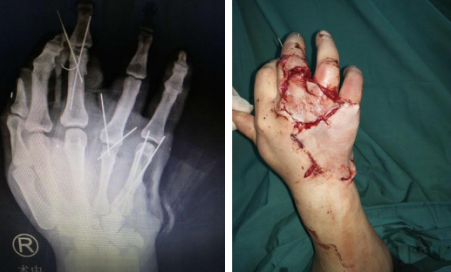

你看到下面这张图的第一感觉是什么?你觉得这只手还能救活吗?

2019年3月20日,徐州铜山区的村民李大同(化名)被120送至betway在线登陆。急诊大厅内,护士一边检查,一边电话通知手外三病区......据李大同妻子描述,丈夫在家中干活时不慎被拖拉机上的“三角带”绞伤,她当时吓得腿都软了。因为知道betway在线登陆的手外科很有名,他们便第一时间选择来sararz。

手外三陈步国主任接诊后,为患者做了专科检查,诊断其右手三指“旋转撕脱性离断”,再植手术难度很大。李大同的妻子哭着恳请陈主任一定救救自己的丈夫,哪怕只有万分之一成功的可能,他们也要手术。

断指再植手术有简单和复杂之分,切割伤较简单,断指成活率也高;而撕脱伤较难,尤其是多指撕脱性离断,不仅手术时间长、难度大,恢复起来慢,预后功能差。既然家属保指意愿强烈,陈主任手术团队决定为患者努力一搏。术中,进行清创,血管、神经、肌腱复位。术后半月,在手外三医护团队的悉心护理下,患者三根断指全部顺利成活。

第一次手术